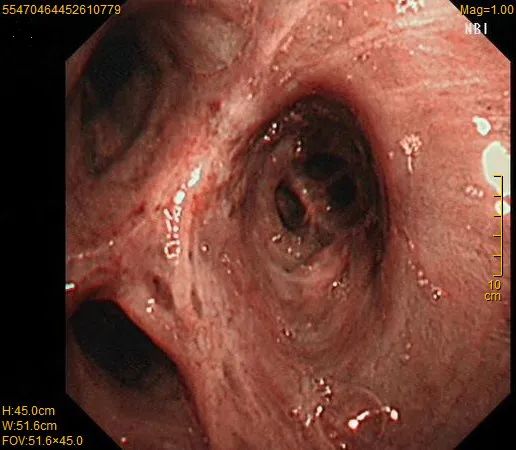

气管镜图:左肺上叶